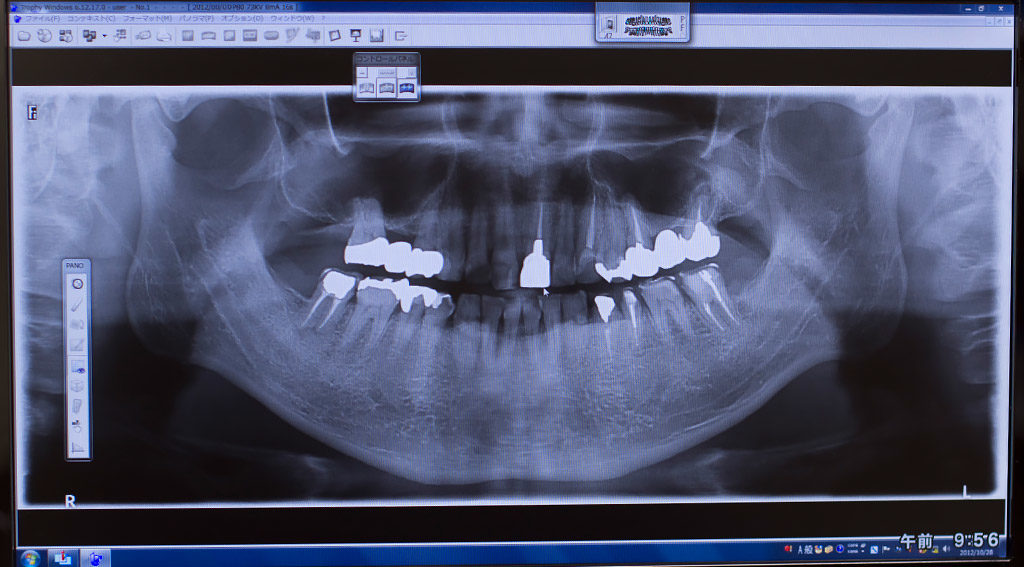

インプラント治療法 歯周病虫歯顎関節症 インプラント治療の前に治すべき口内の病気 2018年8月22日 インプラントの歯は見た目もキレイで自分の本当の歯のようにしっかりと噛むことができます。インプラント治療に影響がでてしまう口内の病気もあるので、しっかりとした検査を受け、事前に治療をしておくことをおすすめします... oita-implant